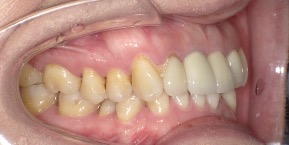

29歳女性のビフォーアフター

| 診断 | 叢生(デコボコがある状態)、過蓋咬合 |

| 治療方針 | インビザラインシステムにて主にIPR(歯と歯の間をわずかに削合してスペースを獲得する方法)を組み込んだ動的矯正治療を行い、叢生を改善後、保定を行う。臼歯部の咬合関係はプランの関係上維持して叢生と前歯部の咬合改善を目指した。 |

| 治療費 ※ | 60万4千円(診断、型取り、PMTC、保定装置を含む料金) |

| 治療期間 | 1年5か月 |

| リスク | 1日20時間以上マウスピースを使用できない場合、歯が動かない可能性がある。装着時や食事時に痛みを伴う。歯肉退縮や虫歯になるおそれがある。また、指導通りに装着できていない場合や適切なブラッシングが出来ていないとそのリスクが高くなる。歯根が短くなることがある。ごくまれに歯の神経が損傷してしまうことがある。過去にぶつけたり深い虫歯治療をしたことがあるとそのリスクはやや高くなる。矯正後には保定装置が必要。適切な使用ができない場合、後戻りの原因となる。将来的に歯並びが動いて再矯正が必要な場合がある。親知らずが正常に生えていない場合、その可能性がやや高くなる。 |